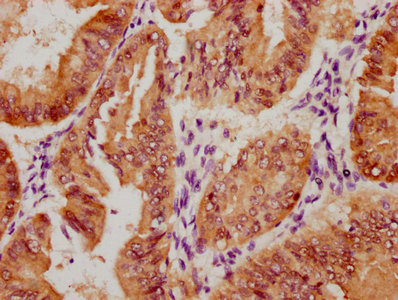

IHC image of CSB-RA555705A0HU diluted at 1:100 and staining in paraffin-embedded human skin tissue performed on a Leica BondTM system. After dewaxing and hydration, antigen retrieval was mediated by high pressure in a citrate buffer (pH 6.0). Section was blocked with 10% normal goat serum 30min at RT. Then primary antibody (1% BSA) was incubated at 4°C overnight. The primary is detected by a Goat anti-rabbit polymer IgG labeled by HRP and visualized using 0.05% DAB.